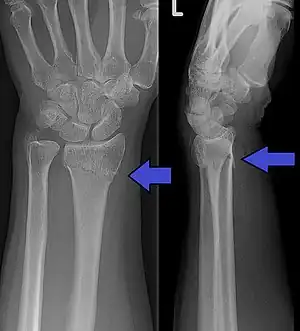

A Colles fracture as seen on X-ray: It is a type of distal radius fracture.

In younger people, these fractures typically occur during sports or a motor vehicle collision.[2] In older people, the most common cause is falling on an outstretched hand.[2] Specific types include Colles, Smith, Barton, and Chauffeur's fractures.[2] The diagnosis is generally suspected based on symptoms and confirmed with X-rays.[1]